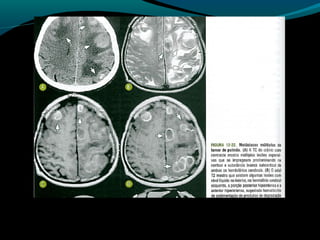

Astrocitoma difuso (GRAU II OMS)

Bem diferenciado;

Grau II;

10 a 15% dos astrocitomas;

Entre 20 a 45 anos;

Crescimento lento;

Tendência para degeneração maligna;

2/3 supratentoriais (frontal e temporal);

Convulsão e cefaléia;

Grau II, tendência à progressão para astrocitoma

anaplásico;

TC:

lesão hipo ou isodensa;

Geralmente NÃO se impregna por contraste ( se sim,

pensar em degeneração maligna);

RM:

Aspecto aparentemente circunscrito mas tumor se

infiltra;

Hipointenso em T1 e hiper em T2 e FLAIR;

Realce pelo Gd no tumor ou leptomeninge  pensar em

degeneração maligna;

Discreta redução do NAA;

Aumento do Co;

Aumento da relação Mi/Cr;

Valores do coeficiente de difusão aparente aumentados;

Baixa perfusão;

Recomendações:

RM associada às técnicas (ERM, difusão, perfusão)

método de escolha para detecção, controle evolutivo,

e controle pós-operatório;